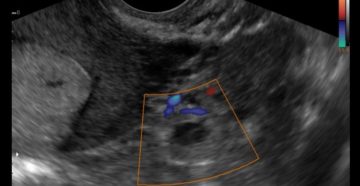

Маточная труба не визуализируется на УЗИ: почему и является ли это нормой Диагностика состояния женской…